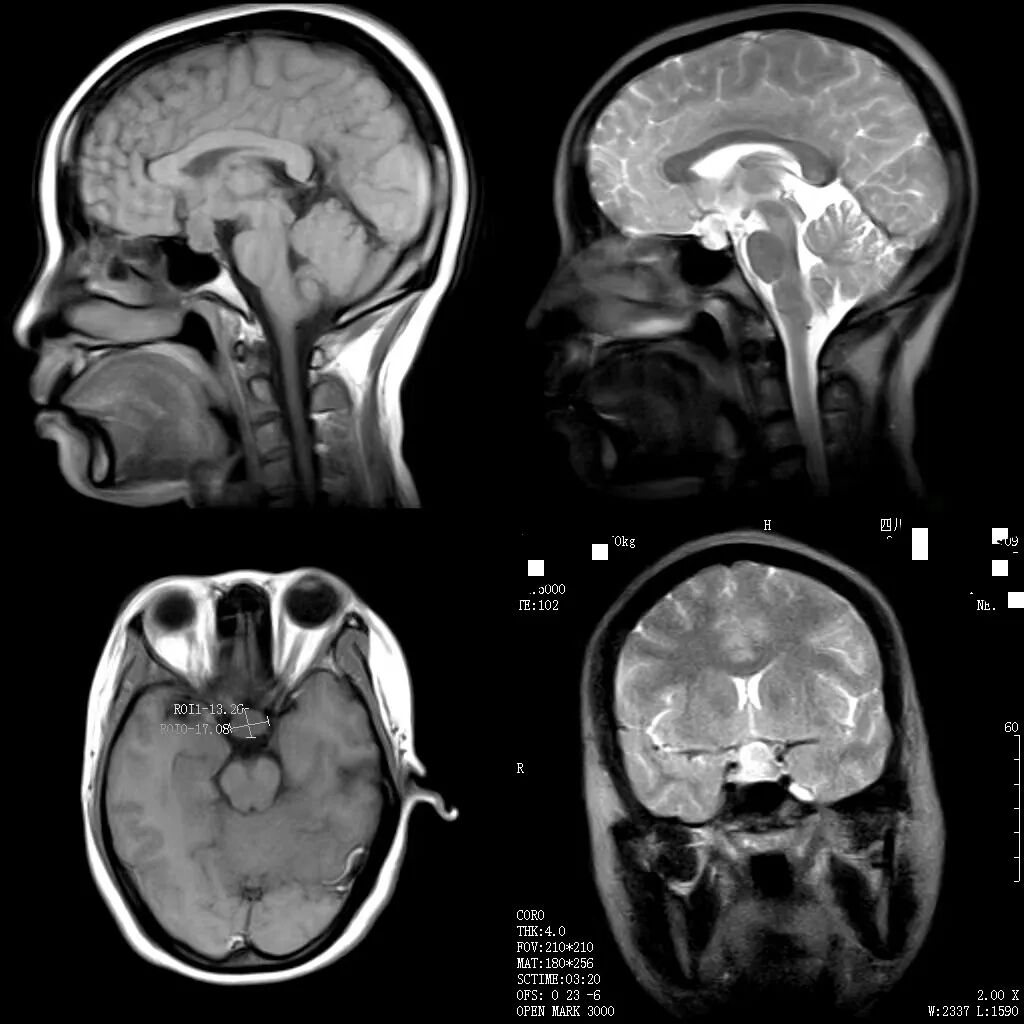

随着医学科学技术的快速发展,磁共振成像(MRI)检查作为一种非侵入性、高分辨率的成像技术,具有广泛的应用范围,已经成为临床诊断中不可或缺的工具。

何军主任以深厚的医学造诣和前瞻性视野,从MRI的基本原理讲起,深入浅出地剖析了磁共振成像的奥秘,检查方法,各类适应症,禁忌症以及最新技术应用等。从理论要点到临床应用,从经典案例到前沿技术,无一不娓娓道来,深刻阐述了MRI技术对于现代临床工作的重大意义。他强调:“MRI以其无创、多参数、高分辨率等独特优势,在中枢神经系统、心血管系统、骨关节及肌肉系统、颈部、腹部、盆腔等病变的诊断中展现出无可替代的价值,希望参与本次培训的医师们能够从中受益,学以致用。”